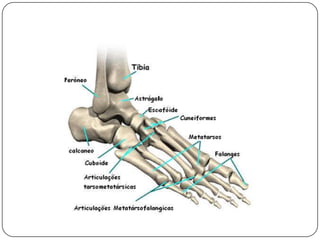

ANATOMIA DO PÉO pé humano é 26 ossos assim distribuídos:

7 ossos do tarso(tálus,calcâneo,navicular cubóide e os três cuneiformes)

5 ossos do metatarso

14 falanges (três para cada um dos dedos, exceto para o hálux, que tem apenas duas).DefiniçãoO pé torto congênito (PTC) é uma deformidade complexa que compromete as estruturas ósseas e partes moles caracterizada, clinicamente,por equino do retropé,varo do calcâneo, adução e supinação do médio e antepé e cavo.